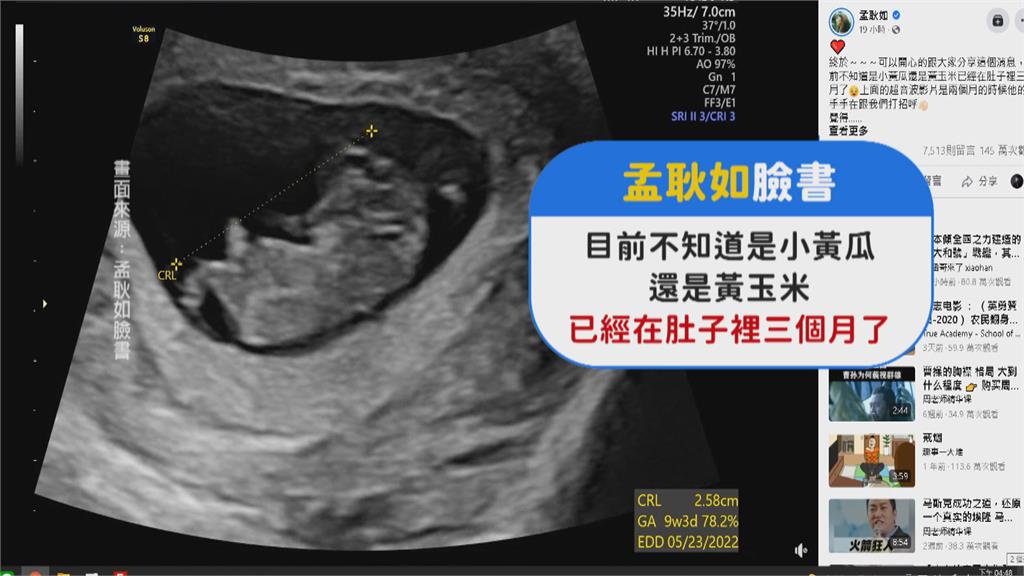

升格準媽媽後,首度對外亮相,臉上洋溢幸福笑容,孟耿如前一天晚上,先在臉書開心公布,已經懷孕三個月,還曬出超音波影片,以後孩子小名打算叫,黃玉米或小黃瓜,預產期大約在明年五月,不過目前還不知道寶寶性別。